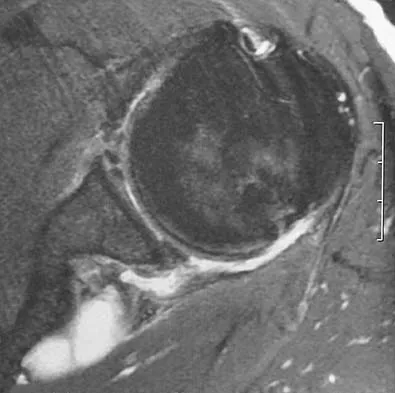

A 28-year-old man reports knee stiffness, swelling, and a constant ache that is worse with activity. Examination reveals an effusion, global tenderness, and warmth to the touch. Flexion is limited to 110 degrees. Figures 48a through 48d show sagittal T1-weighted, sagittal T2-weighted, axial T1-weighted fat-saturated gadolinium, and axial gradient echo MRI scans. Based on these findings, what is the most likely diagnosis?

The MRI scans show multiple low-signal intensity lesions scattered throughout the knee, extending posteriorly inferior to the tibial plateau. The low-signal intensity on both the T1- and T2-weighted images, the modest vascularity noted on the gadolinium image, and the "blooming" noted on the gradient echo image (ferrous-laden tissue) are all strongly suggestive of diffuse PVNS. Whereas synovial chondromatosis can present as diffuse masses in the knee, they present as nodule masses that have low T1- and high T2-weighted signal characteristics. Resnick D (ed): Diagnosis of Bone and Joint Disorders. Philadelphia, PA, WB Saunders, 2002, pp 4241-4252.